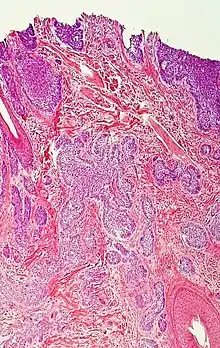

癌细胞具有在显微镜下可见的明显组织学特征。其细胞核通常较大且不规则,细胞质也可能显示异常。